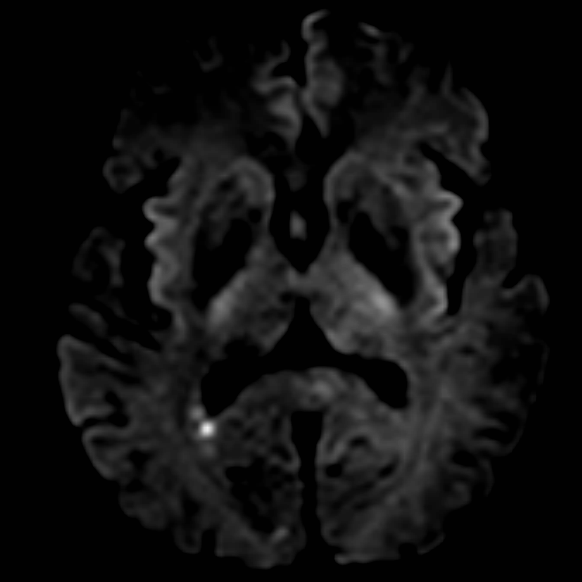

相逢就是缘,有求必全力以赴。立即进行全面评估,CTA和MRI发现颅内多发脑梗塞,脑干为重,双侧椎动脉颅内段基本看不到了,而进一步的DSA造影更为糟糕,左侧椎动脉的颅内颅外段直接全程完全闭塞,右侧颅外剩下一个小尾巴在血液中摇摇欲坠……,诺大的后循环仅仅靠纤细的后交通动脉从前循环借点血液过来,勉强续命,仅仅靠这点前循环的救急,可谓“杯水车薪”,不是“长久之计”,于是决定开通右侧闭塞的椎动脉(颅内+颅外,主要集中在V3+V4段)。